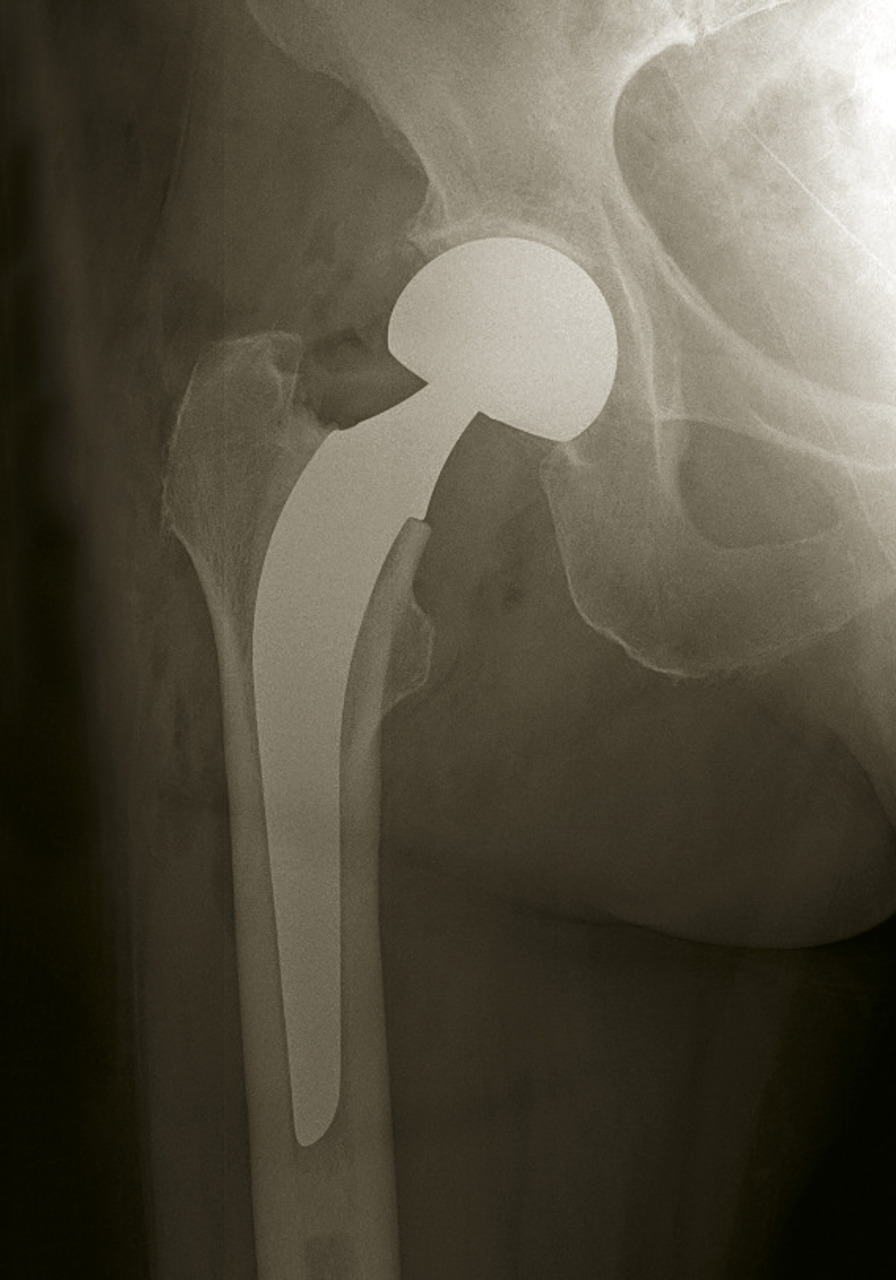

En cas de fracture cervicale vraie Garden III ou IV, le risque de nécrose est important, et il est préférable de s’orienter vers un remplacement prothétique (fig. 14). Il peut s’agir d’une prothèse céphalique où la prothèse remplace uniquement la tête fémorale. Il peut s’agir d’une prothèse intermédiaire qui remplace la tête fémorale mais avec un système de double glissement qui améliore la stabilité de l’implant et diminue les risques d’usure de l’acetabulum. Il peut s’agir d’une prothèse totale de hanche. L’utilisation ou non du ciment pour la fixation de la prothèse ne fait pas consensus dans la littérature, chaque méthode ayant ses avantages et ses inconvénients. Toutefois, chez les patients jeunes, en général de moins de 50 ans, malgré les risques de nécrose, l'ostéosynthèse est conseillée, même dans les fractures Garden III et IV.

Les fractures périprothétiques (fig. 18) : c’est une complication des arthroplasties liée aux chutes fréquentes dans cette population âgée et qui expose au risque de fracture du fémur autour de la prothèse.